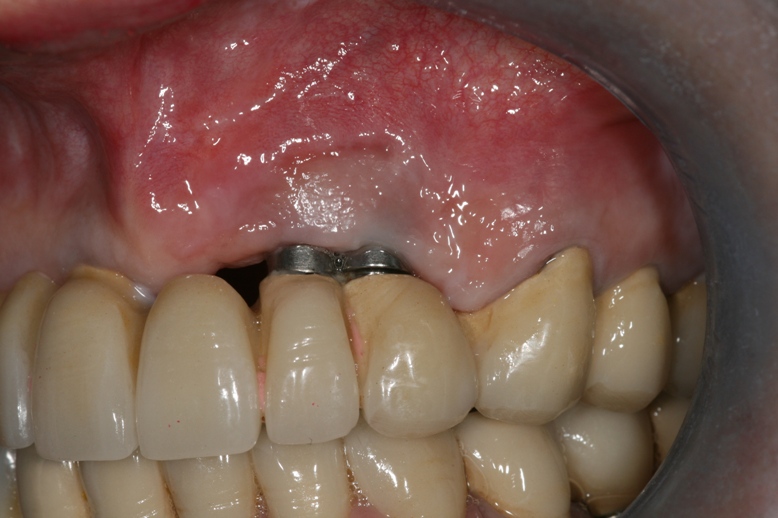

4eme Cas clinique inconnu ! toute la prothèses transvisée sur implant trinon ne sont plus dans l’os il faut tout déposer

!!! Ce patient aurait du recevoir une greffe